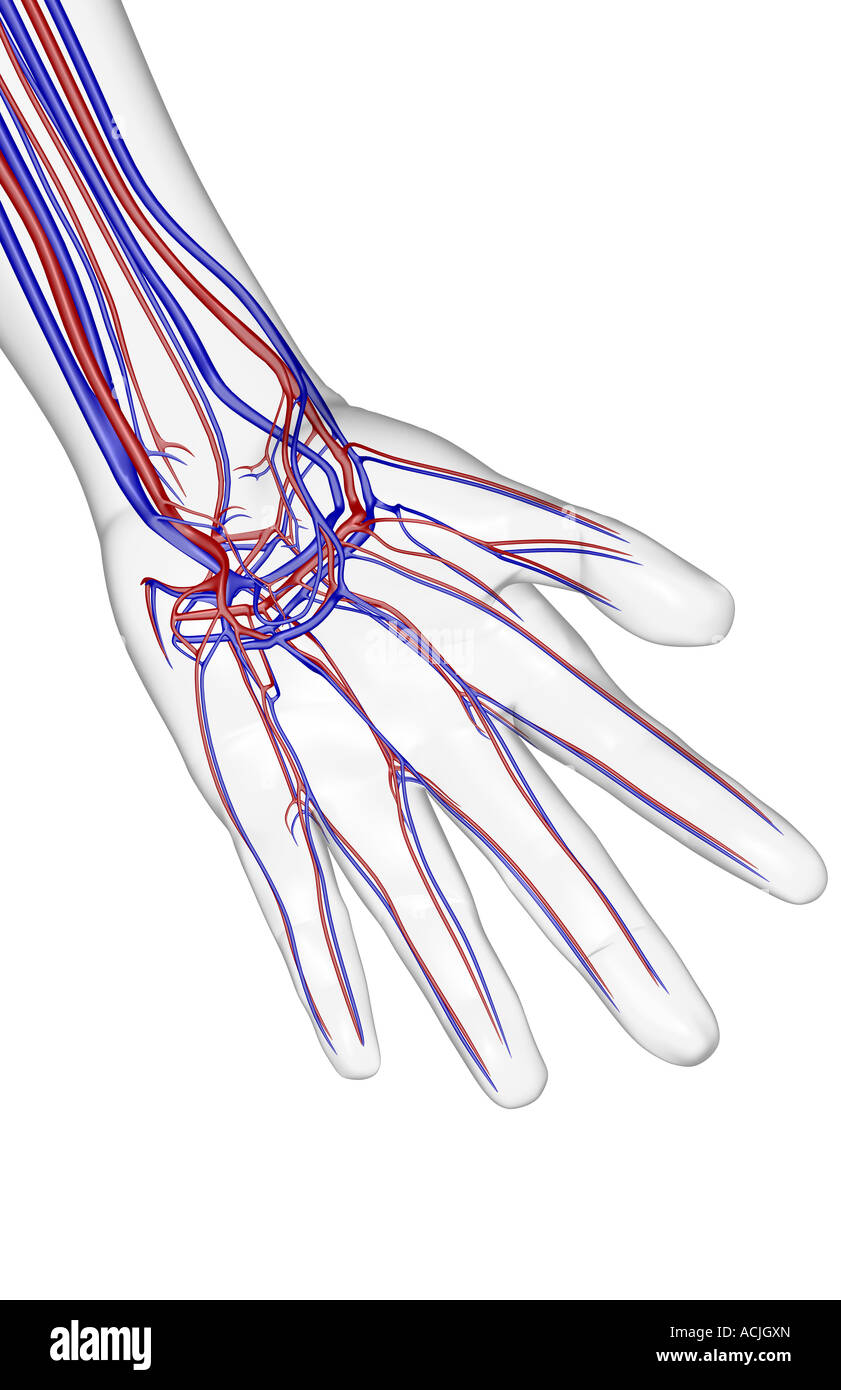

The blood supply of the hand Stock Photohttps://www.alamy.com/image-license-details/?v=1https://www.alamy.com/stock-photo-the-blood-supply-of-the-hand-13174924.html

The blood supply of the hand Stock Photohttps://www.alamy.com/image-license-details/?v=1https://www.alamy.com/stock-photo-the-blood-supply-of-the-hand-13174924.htmlRFACK1NH–The blood supply of the hand